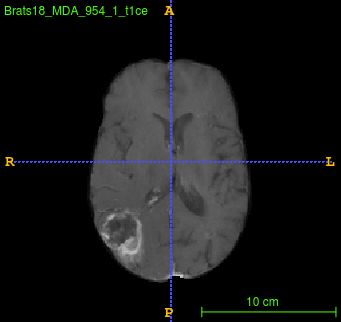

Segmentation of brain tumor from magnetic resonance imaging (MRI) is a vital process to improve diagnosis, treatment planning and to study the difference between subjects with tumor and healthy subjects. In this paper, we exploit a convolutional neural network (CNN) with hypercolumn technique to segment tumor from healthy brain tissue. Hypercolumn is the concatenation of a set of vectors which form by extracting convolutional features from multiple layers. Proposed model integrates batch normalization (BN) approach with hypercolumn. BN layers help to alleviate the internal covariate shift during stochastic gradient descent (SGD) training by zero-mean and unit variance of each mini-batch. Survival Prediction is done by first extracting features(Geometric, Fractal, and Histogram) from the segmented brain tumor data. Then, the number of days of overall survival is predicted by implementing regression on the extracted features using an artificial neural network (ANN). Our model achieves a mean dice score of 89.78%, 82.53% and 76.54% for the whole tumor, tumor core and enhancing tumor respectively in segmentation task and 67.90% in overall survival prediction task with the validation set of BraTS 2018 challenge. It obtains a mean dice accuracy of 87.315%, 77.04% and 70.22% for the whole tumor, tumor core and enhancing tumor respectively in the segmentation task and a 46.80% in overall survival prediction task in the BraTS 2018 test data set.